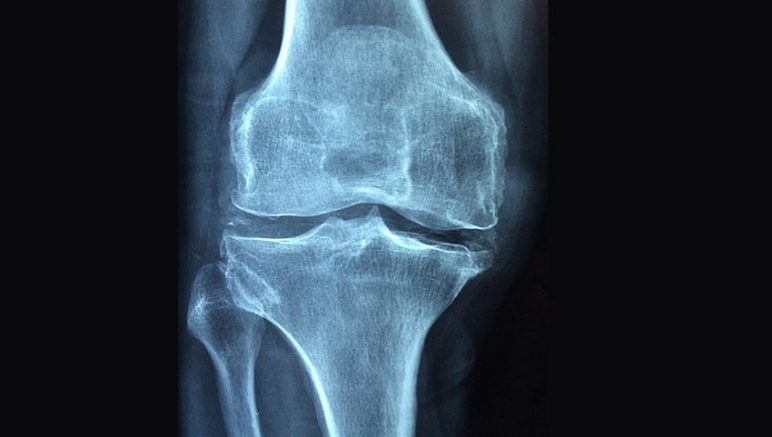

Eklemlerde iltihap sonucunda ağrı, şişlik, kızarıklık ve hareket kısıtlılığı geliştiğini belirten Şahin, "Günümüzde birçok romatizmal hastalık tanımlanmış olup, bunların tanı ve tedavisinde yol alınmıştır. Özellikle iltihabın eşlik ettiği romatizmal hastalıkların çoğunda kas-iskelet sistemi etkilenmektedir." ifadelerini kullandı.

Pek çok romatizmal hastalığın, ilk gözlenen ve en önemli belirtilerinden birinin de eklem bölgelerinde oluşan artrit olduğunu vurgulayan Şahin, şunları kaydetti:

"Artrit bulgusundan yola çıkarak romatizmal hastalıkların tanısının erken konması, dolayısıyla tedaviye bir an önce başlanması hastalığın seyri ve oluşabilecek sakatlık, iş gücü kaybı açısından çok önemlidir. Eklem iltihabı, yani artrit romatizmal hastalıklar dışında bazen başka nedenlerle de ortaya çıkabilmektedir. İşte bunların da ayırt edilmesi ve ilişkili durumların tedavilerinin planlanması önemlidir. Yaşa ve cinsiyete göre romatizmal hastalıkların görülme sıklığı da değişebilmektedir. Bazen de genetik olarak aileden romatizmal hastalıklar belirli oranlarda geçebilmektedir. En önemli nokta eklemde oluşan enfeksiyonun ayırt edilmesidir."